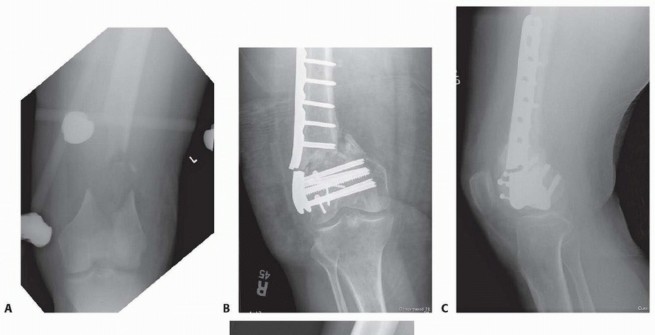

### FIG 5 • A-C. Patient with a spiral distal-third femur fracture that appears to be extra-articular. A. In the AP radiograph, the knee is not fully visualized. B. A dedicated knee AP radiograph shows the spiral distal-third femur fracture. Note the intra-articular injury and the gap at the fracture (arrows). C. Lateral view of the knee. Again note the coronal fracture of the medial femoral condyle (type B3). D-F. Plain radiographs of a patient with a grade II open distal femur fracture. G,H. Patient with a dosed femur fracture that was initially thought to be extra-articular. 470

### FIG 6 • A. Axial CT image of patient in FIG 5A-C confirming the type B3 fracture of the medial femoral condyle. B. Axial CT image of the patient in FIG 5D-F. C-E. CT images of the patient in FIG 5G,H show the nondisplaced intercondylar split as well as the low lateral fracture line and extensive posterior metaphyseal comminution (type C2).

### FIG 7 • AP (A) and lateral (B) views of a three-dimensional (3-D) CT reconstruction of the patient in FIG 3B with a distal femur fracture. The fracture is well defined. C. An oblique 3-D CT reconstruction view showing the same patient and the rotational malalignment between condyles. ## SURGICAL MANAGEMENT 471 The goal of any treatment, nonoperative or operative, is to maintain or restore the congruity of the articular surface and restore the length and alignment of the femur and, subsequently, the limb. Once surgery is deemed appropriate for the patient and the particular injury, the surgical technique options available are determined by the particular fracture pattern. Distal femur fractures have been classified several ways. The OTA/AO classification is probably the most widely accepted classification system and allows some guidance on which techniques are best ( FIG 8; Table 1). Treatment also must be determined based on factors other than the classification alone. The degree of comminution and injury to both the articular surface and bone The amount of fracture displacement The soft tissue injury Associated injuries, other fractures, and injury to neurovascular structures